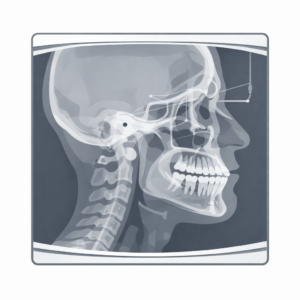

パノラマレントゲン

歯の状態、歯を支える骨、親知らず、埋まっている歯、治療済みの歯の状況などを俯瞰的に把握します。

セファログラム(頭部X線規格写真:セファロ)

矯正治療ならではの検査で、骨格・歯・口元のバランスを規格化した条件で評価できます。

治療計画の根拠を作るメインとなる画像検査です。

セファロは「横顔のレントゲン」というイメージを持たれやすいのですが、実際は治療の設計図を作るための資料です。

治療開始前に、当院では主に次のような項目を評価します。